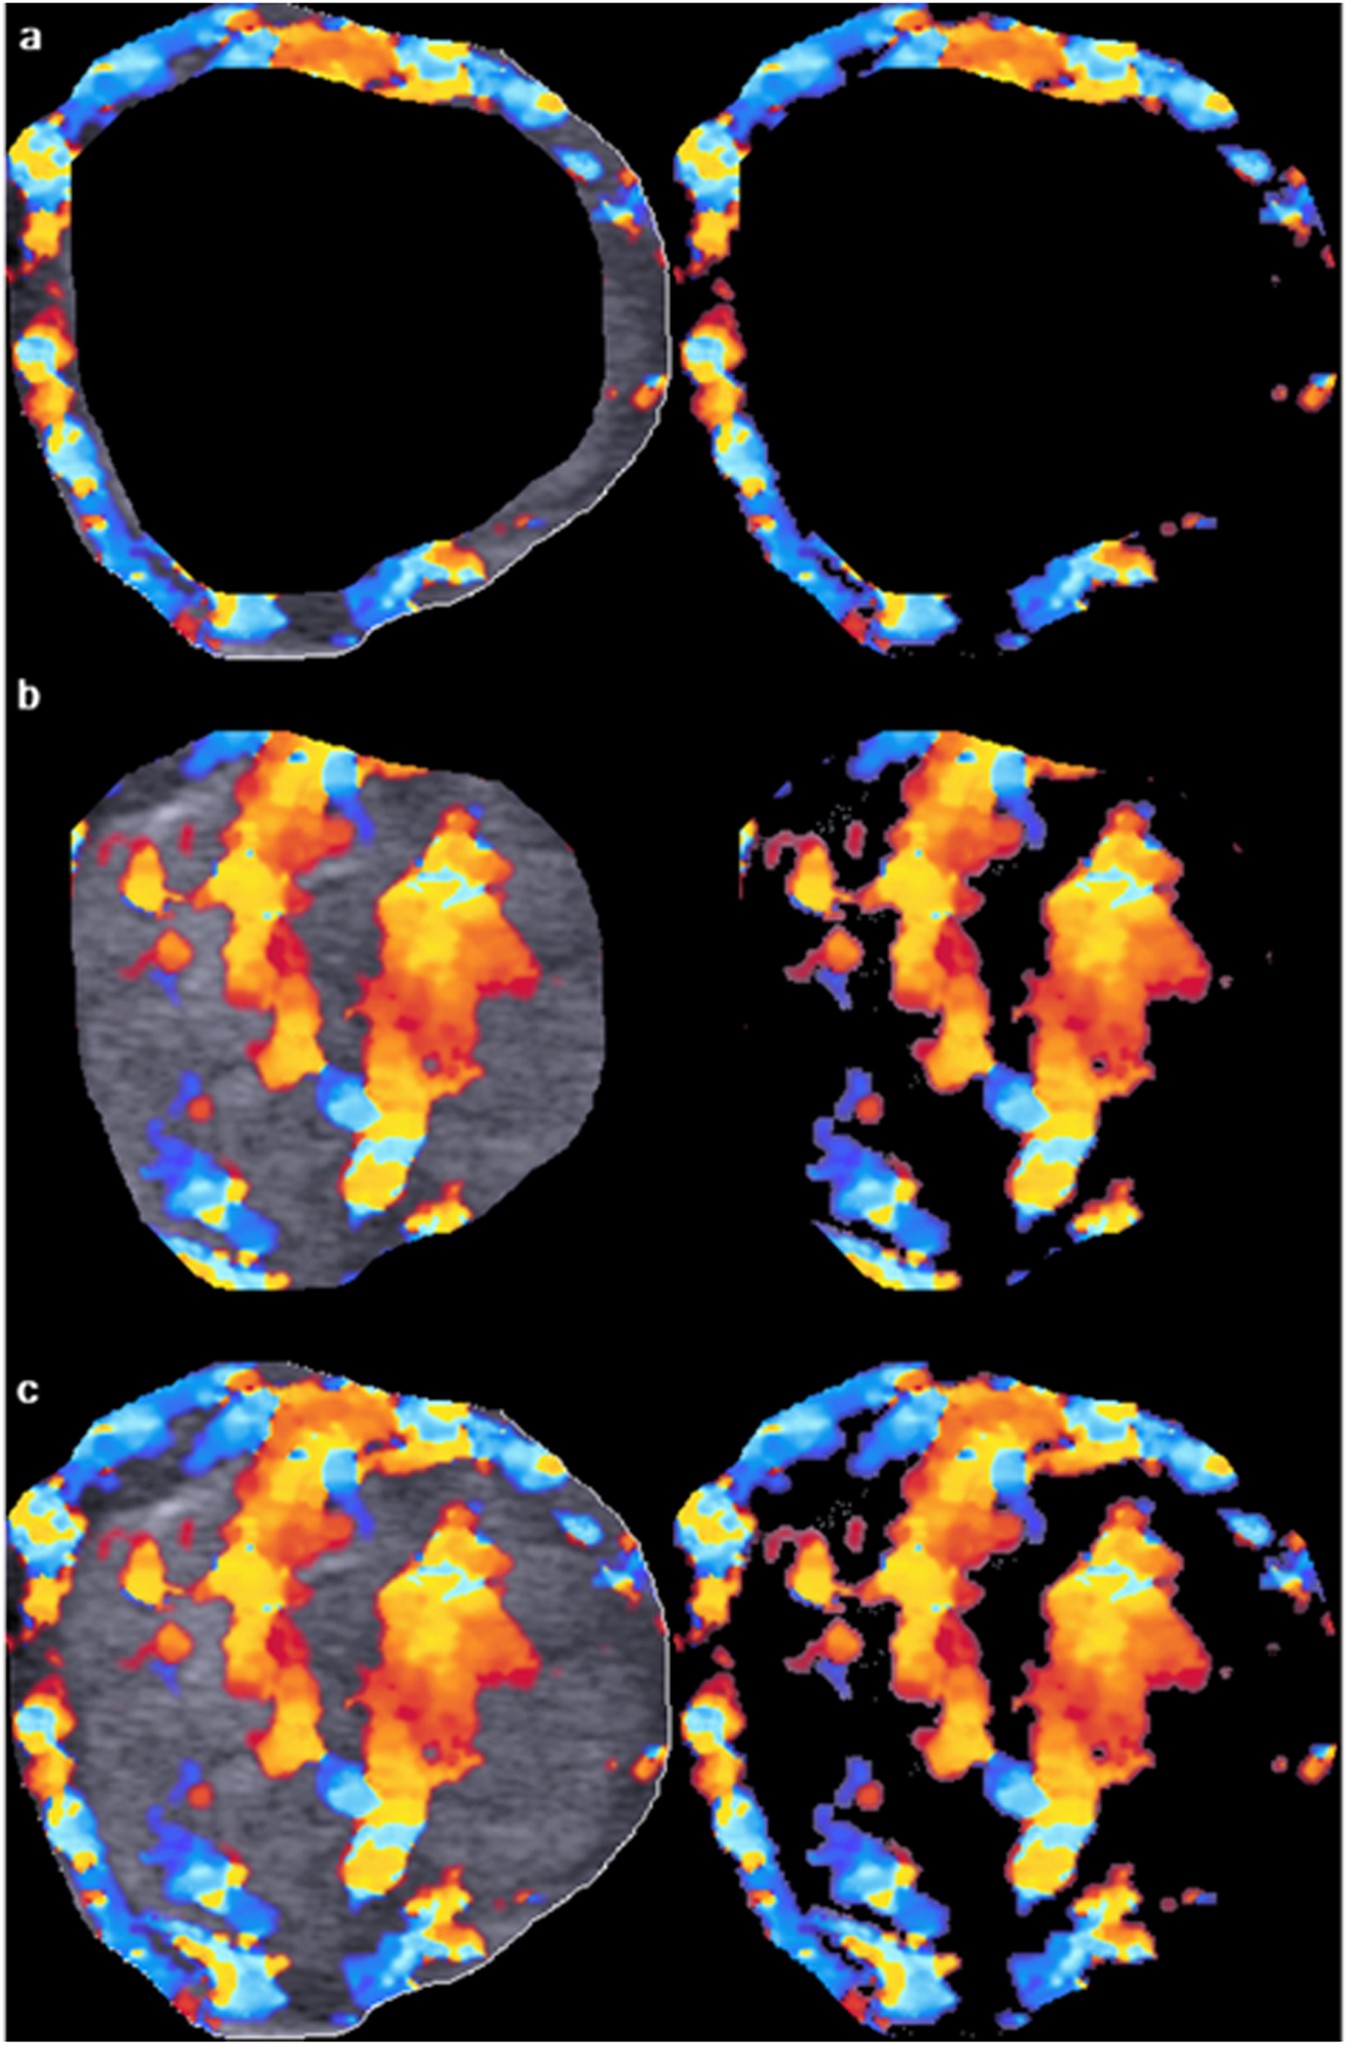

Figure 3

From: Computer-aided assessment of regional vascularity of thyroid nodules for prediction of malignancy

Image analysis of peripheral, central and overall vascular index (VI) of the thyroid nodule as shown in Fig. 2. The primary region of interest (ROI), i.e. the thyroid nodule, was extracted from the outlined area. Using an offset level of 10%, the peripheral (a, left) and central (b, left) regions of the nodule were segmented and the total number of pixel within the segmented area was counted by the computer algorithm. The color pixels coded by the color Doppler ultrasound were extracted by eliminating the grey scale pixels, and the color pixels were counted by the algorithm (a, right and b, right). The VI of peripheral and central regions of the nodule was the percentage of the number of color pixels to the total number of pixels within the segmented area. The overall VI of the nodule was evaluated by counting the total number of pixel within the ROI (c, left) and the number of color pixel in the image with the grey scale pixels eliminated (c, right).